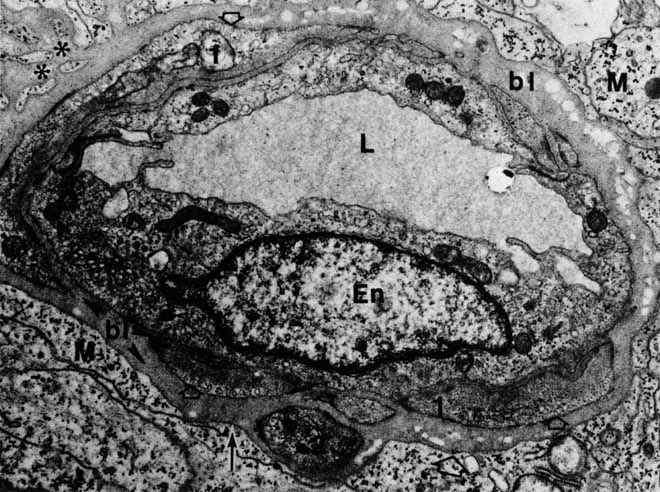

Fig. 23 Main figure. The rod outer segment (R) with discs is surrounded by pigment epithelial villi (arrowheads) and pigment granules (Pi) from the enveloping pigment epithelial cell (original magnification ×48,000). Inset. The interdigitation of the pigment epithelial cells (I) and the rod outer segments (2) places the outer segments near the apical pigment granules. (3) Inner segments. The external limiting membrane (arrowhead) lies internal to this region (original magnification ×720).